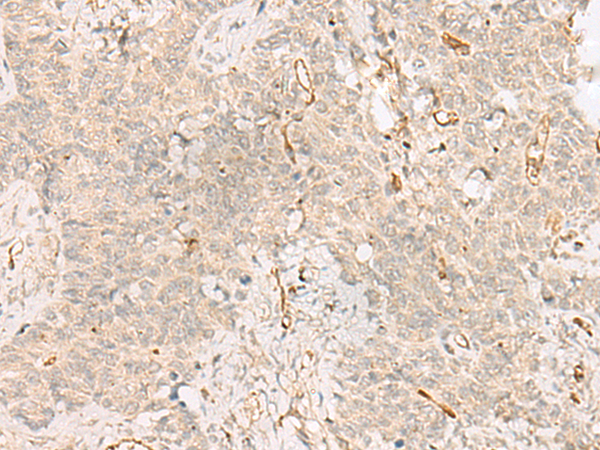

分类: 科研抗体货号: P07155别名: MN; CAIX应用: WB,IHC反应种属: Human